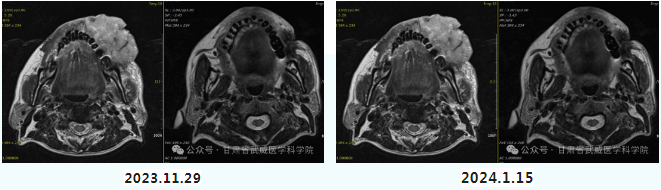

Case 1: Patient Tan**, male, 67 years old. On February 20, 2023, the patient discovered a millet-sized, painless mass on his left buccal mucosa. Later, the mass rapidly increased in size (7×6 cm), with ulceration and purulent discharge on the left cheek, accompanied by limited mouth opening. Biopsy showed: high-grade intraepithelial neoplasia of the left buccal mucosa. The mass on the left cheek had increased to a size of 63×37.1×44.8 mm, accompanied by perforation of the buccal mucosa, invasion of the upper alveolar ridge, and metastasis to double-layer cervical lymph nodes. The patient was admitted to our hospital on November 26, 2023, and received heavy ion radiotherapy starting on December 6, 2023, with a prescribed dose of 69 Gy (RBE)/23 Fx. He also received 4 cycles of TP regimen chemotherapy. Currently, the tumor has basically subsided, the buccal mucosal perforation has healed, pain has significantly relieved, and mouth opening is about two and a half fingers wide.

a comparison of MRI scans before and after treatment

The patient has now completed the fourth cycle of chemotherapy in our department. The mass on the patient's cheek has completely subsided. Three months after the heavy ion therapy, the efficacy was evaluated as Complete Response (CR). The patient expressed that during their hospitalization in the oral surgery department of West China Hospital, seeing other patients who had undergone surgery made them lose confidence in the future. Even though they were about to undergo surgery for the second time after queuing for admission again, upon discovering a second radical treatment option, they resolutely chose the Gansu Wuwei Heavy Ion Hospital. The outcome demonstrates that the patient's choice was correct.